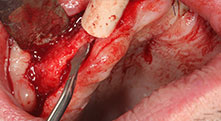

Pourriez-vous décrire brièvement par exemple comment vous procédez pour mobiliser les blocs osseux en vue d’une greffe ?

Pr Bratu : Nous préférons prélever l'os sur la crête oblique externe de la mandibule postérieure, et non dans la région interforaminale. Après l'incision des tissus mous, nous utilisons les nouvelles scies pour définir la quantité d'os à prélever. De la même manière, nous les utilisons également pour la totalité de la préparation dans presque 80 % des cas. Nous avons également parfois recours à d'autres instruments piézoélectriques et, pour terminer, à un burin pour mobiliser le bloc. Nous trouvons cette technique chirurgicale très efficace.

Accepteriez-vous de nous confier quelques astuces chirurgicales courantes dans votre hôpital ?

Pr Bratu : Nous avons volontiers recours à la technique sandwich pour les augmentations mandibulaires latérales. La préparation d'un couvercle osseux est réalisée à l'aide de la scie piézoélectrique et le fragment crestal est fixé à l'aide de microvis. Nous plaçons un mélange de matériau de substitution osseuse autologue et xénogénique entre les deux. Cela fonctionne très bien. Il faut toujours s'assurer que les coupes verticales aient des dimensions suffisantes lors du clivage de la crête alvéolaire dans la mandibule. Sinon, l'os risque de se casser facilement.